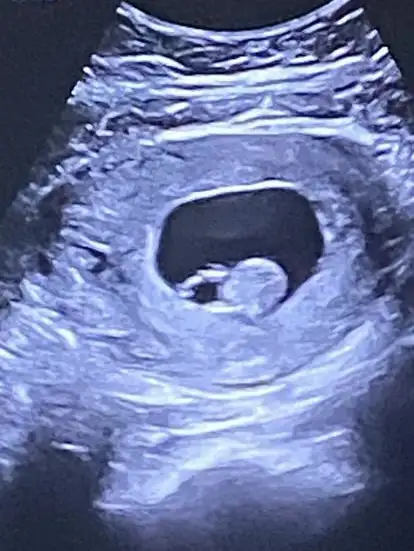

Normal demi canım yolk boyutu

normal normal hıc korkma, 6mm sonrası sıkıntıymıs ..

benım ılık gun 4,3 mm di.. ilk ölçümde 5,5 mm bıraz buyuk gıbı demıstı doktor tekrar baktık 4,3mm cıktı..

10gun sonra kuculmus zaten, cok sukur..

bebe buyudukce kuculuyo

Baksana şunun kesesine canım ben erkek diyorum oval olunca Allah'ım sen sağlıkla nasip et